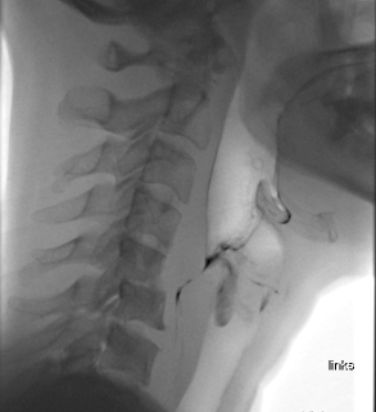

Videofluoroskopie_Aspirtation bei Flüssigkeit.png

Die Auswirkungen einer Schluckstörung, z.B. nach einem Schlaganfall, bei einer Demenzerkrankung oder einem Tumor im Mund-Rachen-Bereich, auf die Lebensqualität und die Gesundheit sind weitreichend. Lange wurden Schluckstörungen mit Anpassungen wie Eindicken von Flüssigkeiten oder Pürieren von fester Nahrung behandelt. Viele jüngere Studien zeigen aber, dass Eindicken keine Komplikationen verhindert. Denn der Körper reagiert mit einer Reihe von Schutzmechanismen, wenn fremdes Material in die Lunge gelangt. Für die Lunge sind aber die Bakterien im Mund am gefährlichsten. Deshalb ist es wichtig, dass die Zähne regelmässig mit Zahnbürste und Zahnpasta geputzt werden, auch wenn man aufgrund einer Schluckstörung gar nichts essen oder trinken kann. Eingedickte Flüssigkeiten führen zusätzlich zu einer feinen Schicht auf der Mundschleimhaut, wo sich die gefährlichen Bakterien besser absetzen und vermehren können. Dadurch steigt das Risiko für eine Lungenentzündung.

Es kann bei einer Schluckstörung vorkommen, dass die Muskelkraft zum Kauen nachlässt. Dies kann dazu führen, dass ein Stück des Steaks die Luftwege blockiert. Diese Gefahr muss logopädisch abgeklärt werden. Das bedeutet aber nicht zwingend, dass das Steak püriert werden muss. Eine Alternative kann sein, es in weiche Würfel kleiner als 1,5 cm zu schneiden (Mindestgrösse der Luftröhre). Mit dieser Kostform wird die Kaumuskulatur ohne das Risiko einer Blockierung der Luftwege trainiert. Im Vergleich zur pürierten Kost bleiben sogar weniger Reste im Hals stecken, die unbemerkt und kontaminiert mit Bakterien in die Lunge gelangen können.